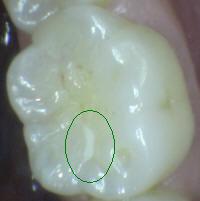

0 |

No obturado ni

sellado. |